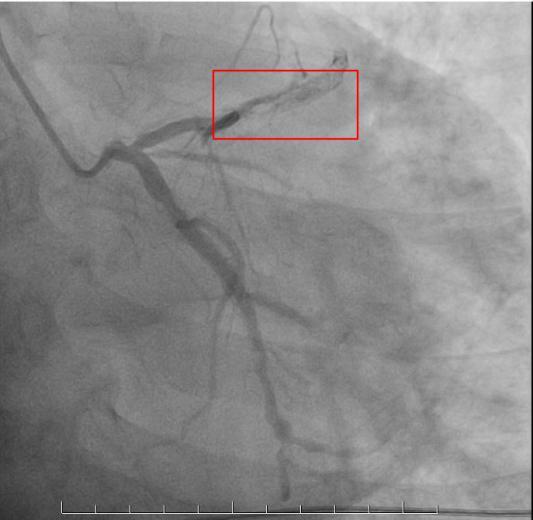

在心血管领域,微创介入手术已成为一种领先的治疗方式,这种先进的手术技术无需开胸,只需通过微小的创口,使用精密的导管技术,就能对心脏血管进行疏通,它不仅大大减少了患者的痛苦,也显著缩短了恢复时间。